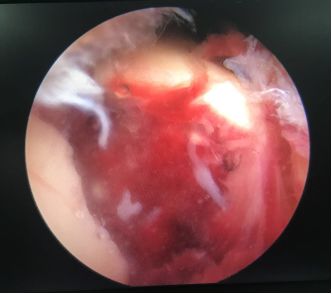

镜下见关节面明显塌陷

镜下检查关节面复位情况